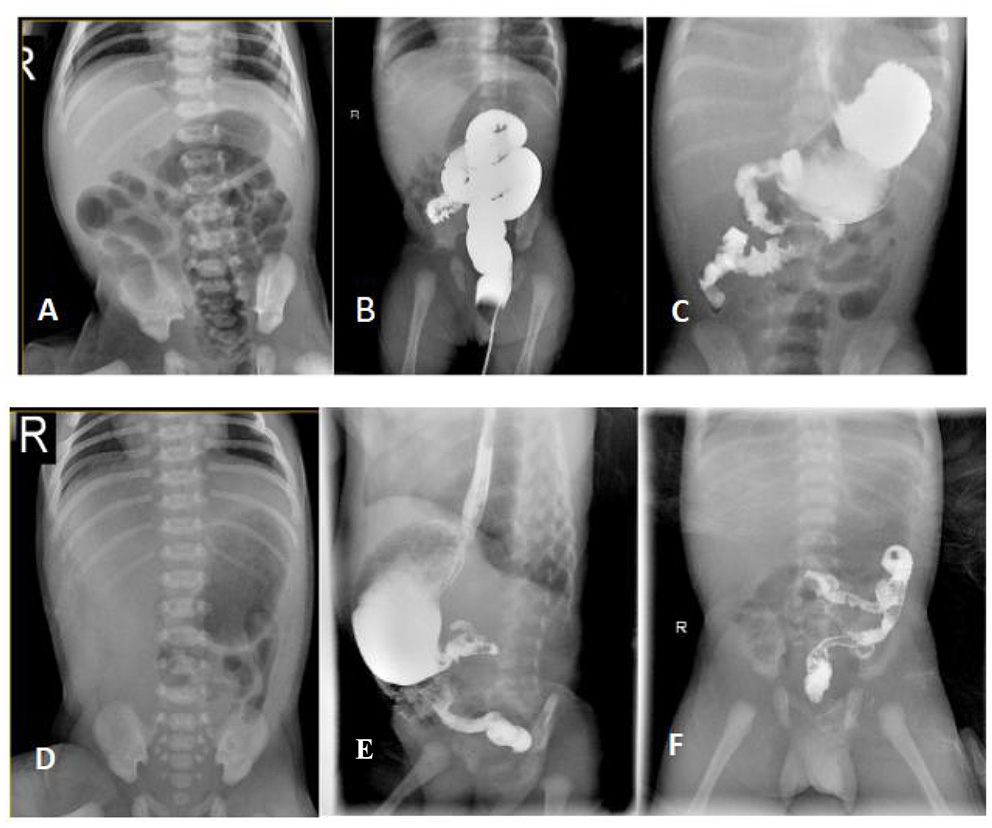

A full-term female baby (II:2) with a birth weight of 2,550 g presented with recurrent vomiting soon after birth (Figure 1). On physical examination, the girl's abdomen was flat and soft, without distention, and the bowel sounds were normal. Blood tests showed that serum potassium was 2.69 mmol/L. X-ray presented the gas-filled stomach and the intestinal loops (Figure 2A) while the colon is mainly located in the center and left side of the abdomen (Figure 2B). Other blood investigations were normal. An upper gastrointestinal series (UGI) revealed intestinal malrotation (Figure 2C). The patient underwent Ladd's operation. At operation, the pediatric surgeon found that the total length of her bowel was only 65 cm from the duodenum to the ileocecal valve. After the operation, the girl initially developed diarrhea during breastfeeding, but gradually developed intestinal tolerance after changing to hydrolyzed milk and continuous nasogastric tube infusion. Parenteral nutrition (PN) was administered for up to 4 months. Fortunately, the child did not suffer from sepsis and liver failure.

Figure 2. Radiological findings of the patients with CSBS. [The proband] (A) X-ray abdomen showing the gas-filled stomach and the intestinal loops; (B) Lower gastrointestinal radiography showing the distribution of the colon predominantly in the center and on the left side of the abdomen; (C) UGI showing the upper part of the jejunum located on the right side of the abdomen in a spiral pattern. [The younger brother] (D) X-ray abdomen showing minimal gas in the stomach with no obvious gas shadows in the intestine. (E,F) UGI showing the ascending part of the duodenum and the upper part of the jejunum in a spiral pattern.

The patient's younger brother (II:3)showed a minimal gas in the stomach with no obvious gas shadows in the intestine using X-ray test, and was diagnosed with malrotation by UGI after birth (Figures 2E,F), and the length of the small intestine was 51 cm during the operation. After the operation, he was also managed similarly with continuous enteral nutrition (EN) supported by PN. His dependence for PN lasted for 40 days. Their parents were not close relatives. They were in good health and denied any history of exposure to poisons, drugs, or radiation. No abnormality was found during prenatal examination in both patients. At the last follow-up, the proband was 3 years and 10 months old, weighing 12.5 kg with a height of 96.5 cm corresponding to P3–P15 as per the 2006 WHO Child Growth Standards (17). Her diet is similar to that of a girl her age, and she can eat meat, vegetables and rice. Similarly, the younger brother was 14 months old, weighing 8.5 kg (P3–P15) with a height of 78 cm (P50). He is currently formula fed. When the siblings were evaluated for intelligence and motor behavior in the child care department, doctors found no significant neurodevelopmental deficits.